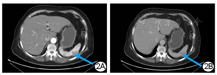

2017年4月7日大连医科大学附属第一医院门诊复查腹部增强CT示:脾脏上极椭圆形稍低密度占位,大小3.0 cm×2.0 cm,增强扫描三期CT值分别为83、78、78 HU,余腹腔脏器均未见异常,腹膜后未见异常淋巴结影(图2)。影像学诊断:(1)脾脏上极肿物,考虑淋巴瘤可能性大;(2)脂肪肝征象。复查胸部CT及全身骨扫描等均未见原位复发及骨转移。鉴于该患者既往乳腺癌病史,影像学仅发现脾脏占位,考虑罕见的孤立性乳腺癌术后脾脏转移,手术指征明确,遂于2017年4月17日全麻下行腹腔镜下脾切除术。手术顺利,术程约2 h,出血少量,常规护理6 d后患者康复出院。术后病理示:脾脏表面一灰黄色结节样肿物,大小3.5 cm×2.5 cm×0.9 cm,切面实性、灰白间灰黄色,与周边分界欠清。镜下见大量异型细胞取代正常脾脏组织,异型细胞大小不一,核大、深染,呈片状或巢状生长。病理诊断:脾脏转移性低分化腺癌,考虑乳腺恶性来源(图1B)。免疫组化:ER(+),PR(-),Her-2(+)。术后随访1年余,患者终因肝转移死亡。